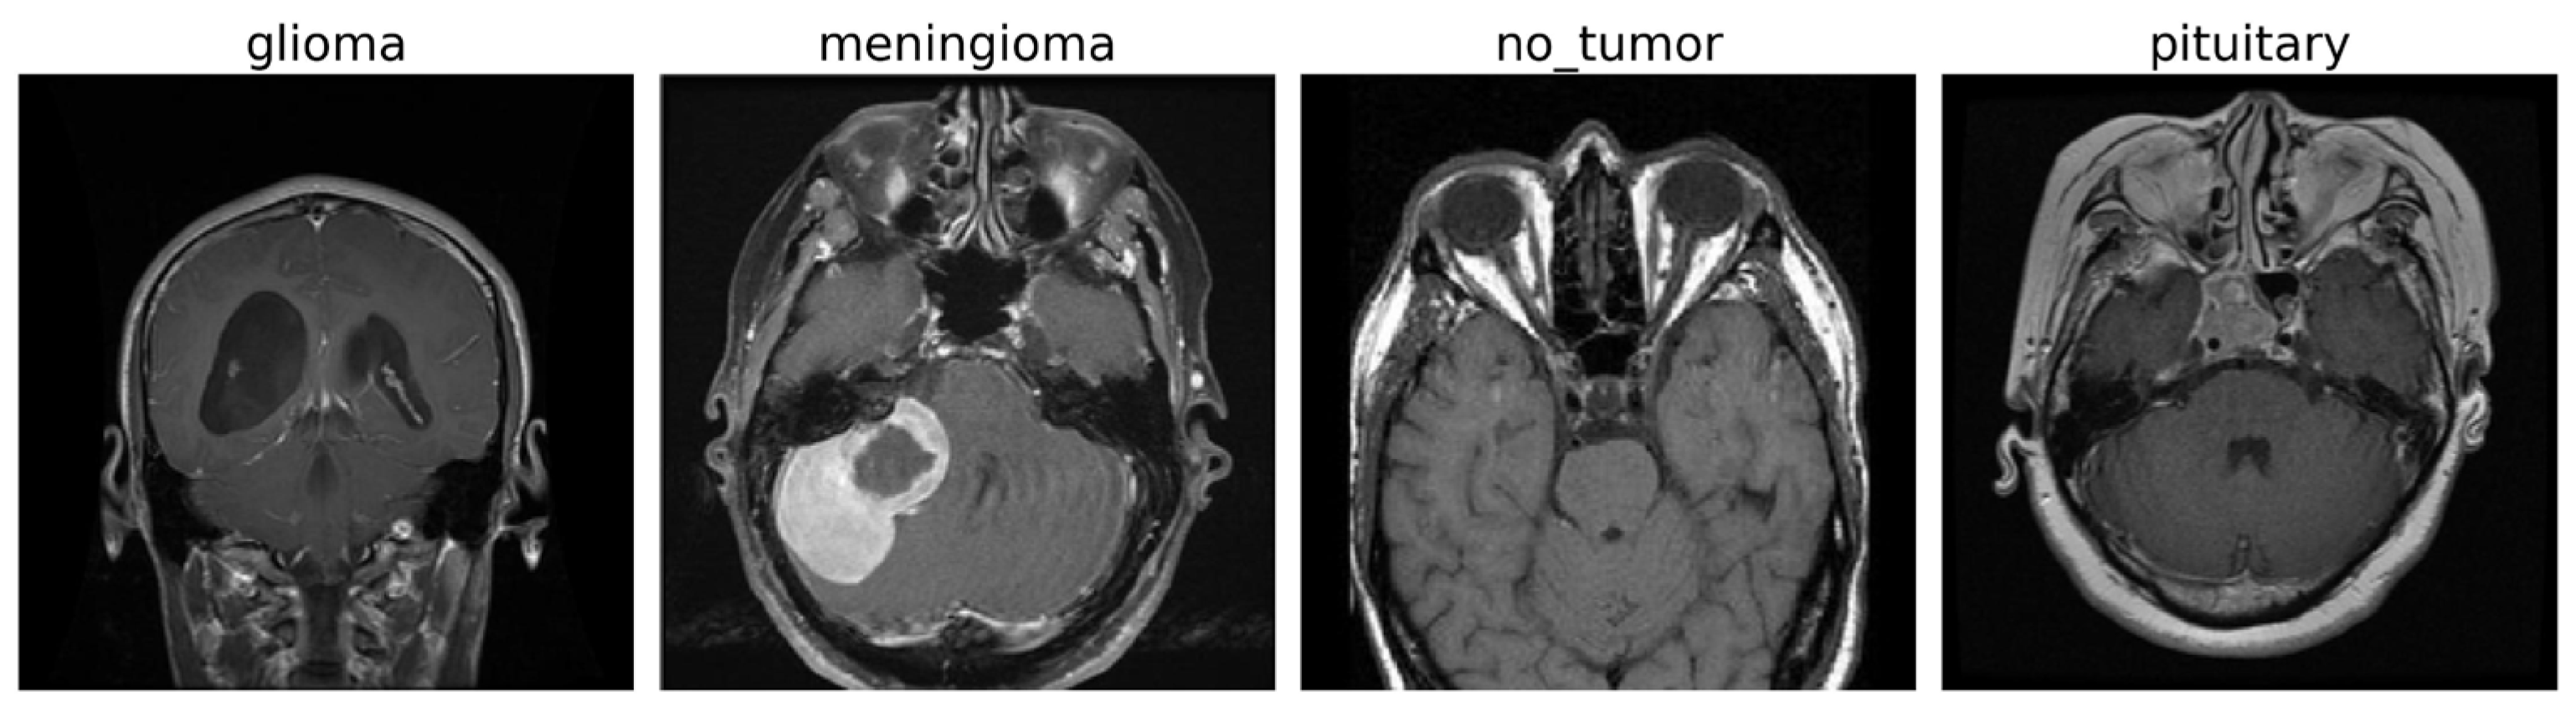

4.1. Dataset